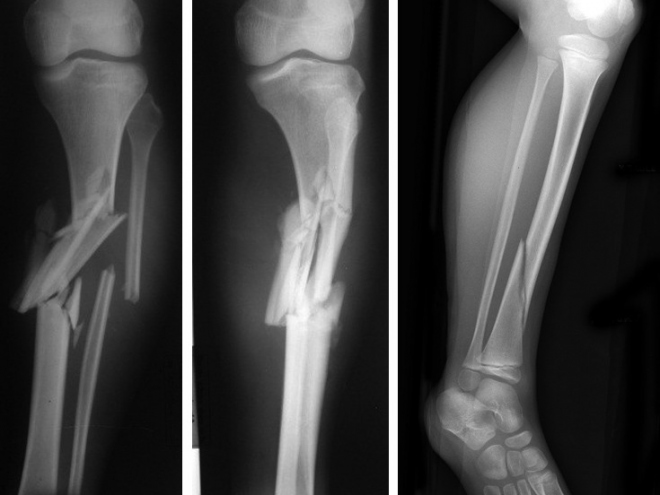

Τα κατάγματα της κνήμης και ειδικότερα τα συντριπτικά έχουν χαρακτηριστική εμφάνιση. Το σκέλος έχει μεγάλη παραμόρφωση, μεγάλο οίδημα και παραφύσιν κίνηση (κουνιέται προς όλες τις κατευθύνσεις) προκαλείται οξύς πόνος!

Τα κατάγματα αυτά (ανοικτά-επιπεπλεγμένα) συνήθως αντιμετωπίζονται με ακινητοποίηση με σύστημα εξωτερικής οστεοσύνθεσης. Τα κλειστά κατάγματα της κνήμης αντιμετωπίζονται με ενδομυελική ήλωση.